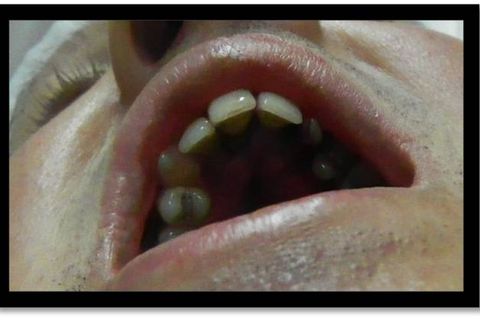

Paciente com palato atresico, com indicacação de ortodontia, apresentou o 23 e 18 incluso e impactado. Optou-se por fazer remoção em duas etapas, primeiro o 23 e após 15 dias o 18. Usou-se como anestésico mepiadri 2% 3 tubetes infiltrativa por vestibular e palatina, descolamento por lingual de 13 á 24 devido a atresia. Houve exposição do plexo da fossa incisiva, mas com sangramento dentro da normalidade, fez-se acesso endodontico e utilizou-se uma lima endodontica após a divulsão dos tecidos para remoção do dente com menor dano ao paciente.

Fotos do caso